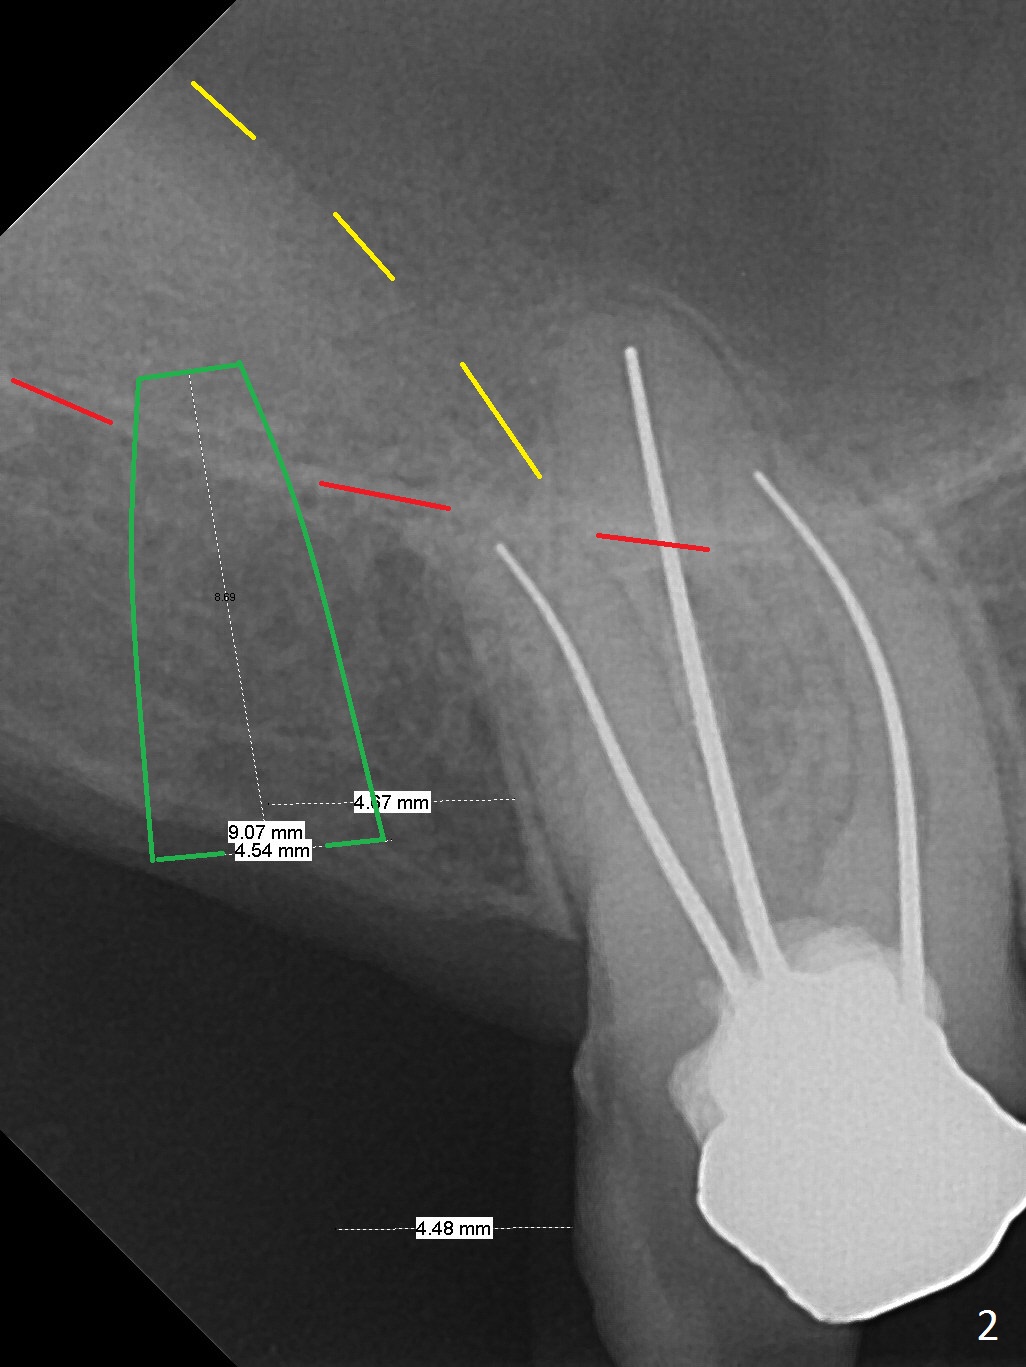

A 59-year-old man had #2 extracted approximately 4 months earlier (Fig.1 pink: possible buccal sockets; blue: palatal one). The edentulous ridge seems to be wide with exostosis (Fig.2 yellow line). Use Magic Split for access and initial bone expansion, followed by Magic expanders. The initial depth will be 7 mm to avoid sinus membrane perforation. Place PRF membranes and bone graft prior to inserting a 4 mm dummy implant. Periodontal dressing may be applied to the rugged surface of the tooth #3 for increased retention. Or a splinted provisional will be fabricated.